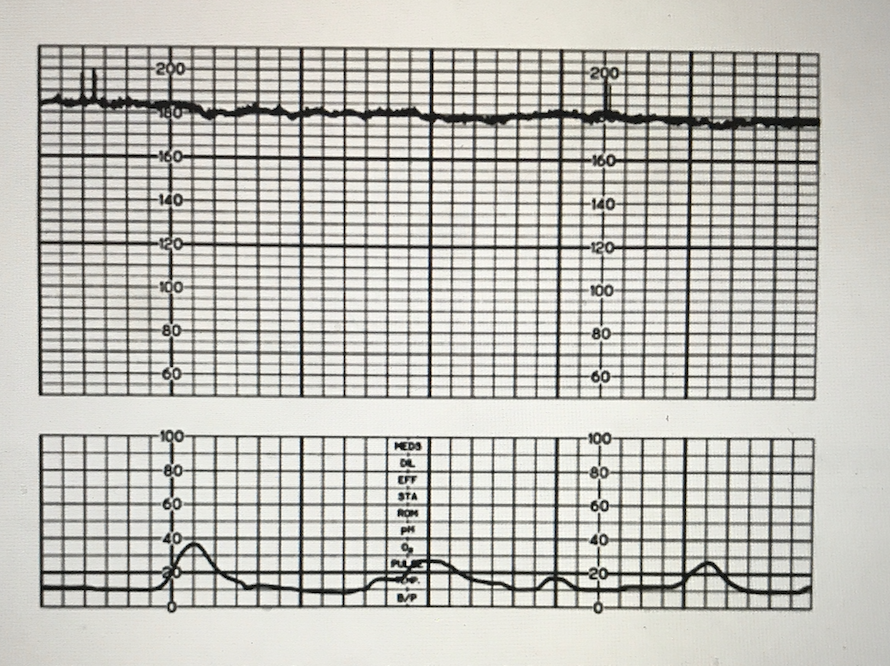

fetal heart tracing in maternal fever

tachy and loss of variability

sinusoidal heart tracing

fetal anemia, autonomic nervous system dysfunction. OMINOUS SIGN.

tachysystole

>6 contractions in 10 minute period